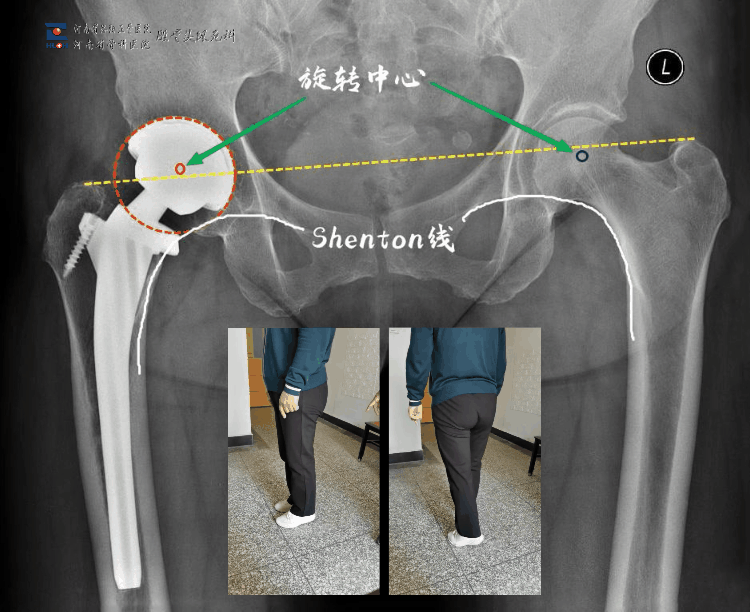

病人之前选用国产某小众品牌关节做了左侧置换,术后下肢变长,又因长时间卧床导致废用性骨质疏松,髋臼安装过高致旋转中心上移出现行走乏力、不协调,假体近端过宽、应力大导致大腿痛;我们采用了另一品牌的关节,根据对侧情况适当调整了肢体长度、旋转中心,使得双下肢能够在行走时协调一致,且选择了合适的假体,避免了股骨近端应力集中,术后第2天下地行走,避免了废用性骨质疏松;病人明显体验不一样的手术效果。